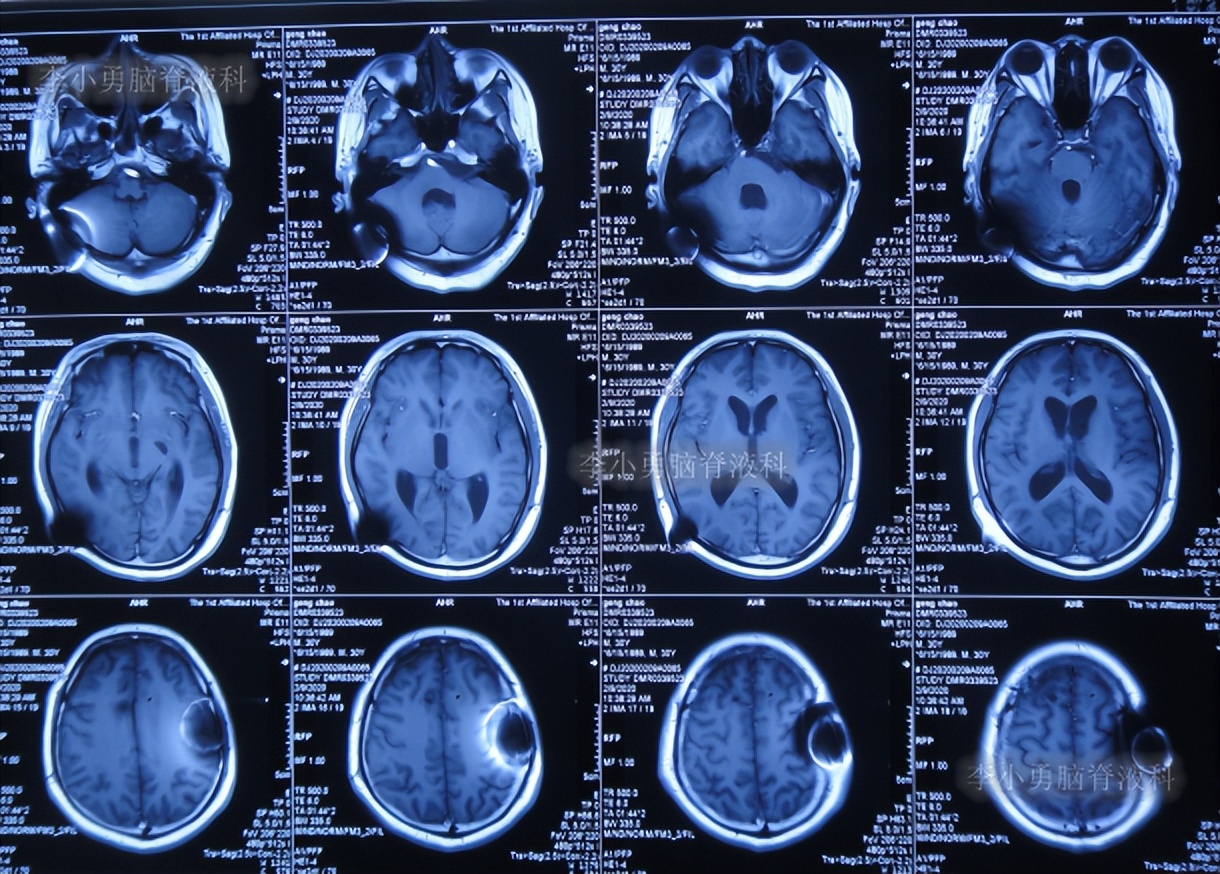

第2次的左侧脑室腹腔分流术后40天即2020年2月9日,查头颅核磁示脑室稍有扩张(图-10)。

图-10:2020年2月9日头颅核磁

第2次的左侧脑室腹腔分流术后44天即2020年2月13日,查头颅核磁示脑室较2020年2月9日有扩张(图-11),未给予特殊处理。

图-11:2020年2月13日头颅核磁